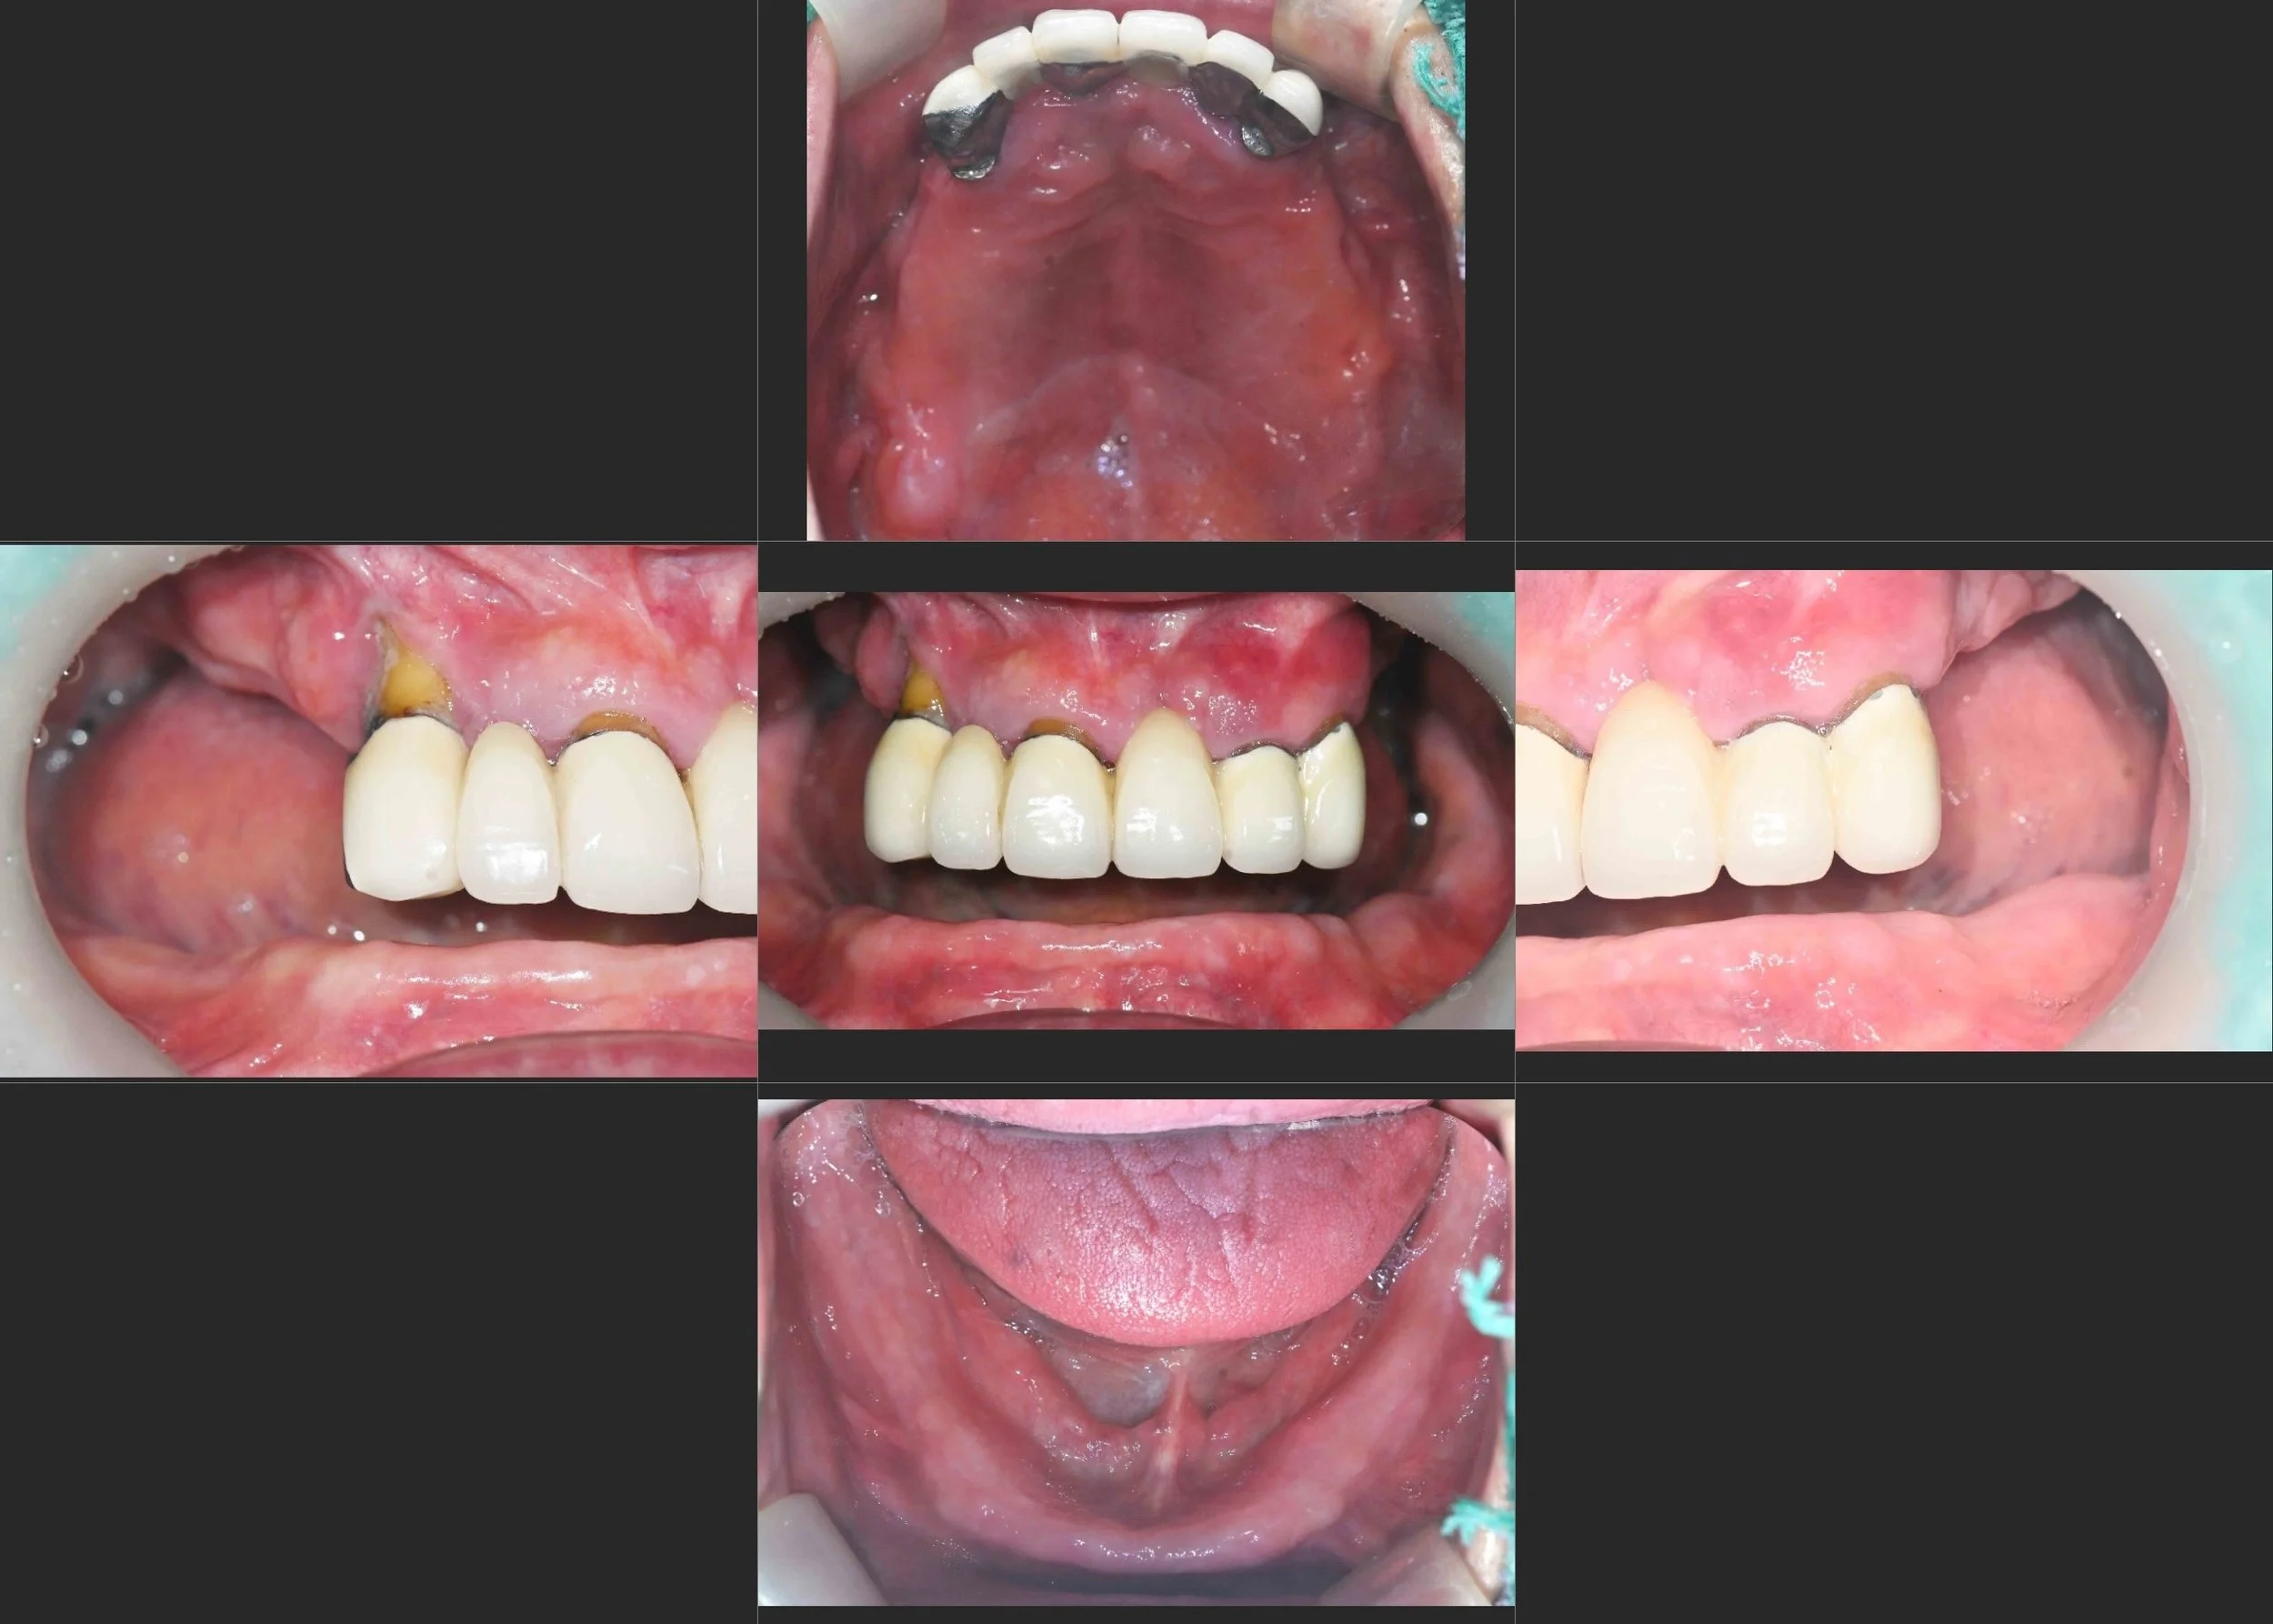

31. Full-Arch All-on-6 Rehabilitation: Overcoming Severe Bone Atrophy and Flabby Tissue

Transitioning from unstable, ill-fitting dentures to definitive fixed stability in a female patient in her 60s. A comprehensive Maxillary and Mandibular All-on-6 reconstruction to resolve chronic "Flabby Gum" syndrome.